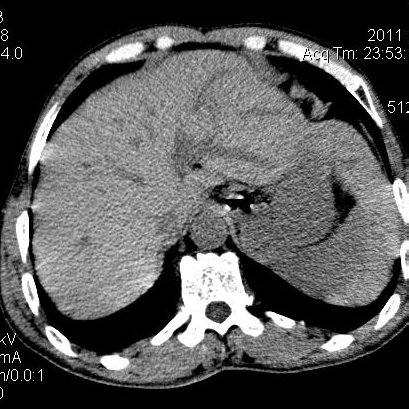

肝左叶发育异常

男性,55岁,骑摩托车摔倒后入院,自述右上腹疼痛

[backcolor=#FF0000]第一次诊断的时候也是这么肯定,可是床旁超声检查并没有发现明显异常,而且患者的一般症状都良好。还好临床只是保守治疗,没有立即手术,第二次复查的时候没有一点变化,又做了MRI检查,没有血肿,

这是一例肝左叶发育异常的,很个性吧~[/backcolor]